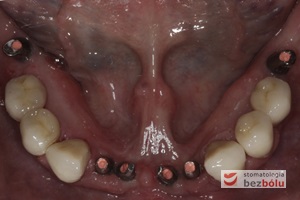

Żuchwa - widok powierzchni okluzyjnej - symetryczne braki zębowe w zakresie 4 siekaczy i trzonowców

Żuchwa – widok powierzchni okluzyjnej – symetryczne braki zębowe w zakresie 4 siekaczy i trzonowców